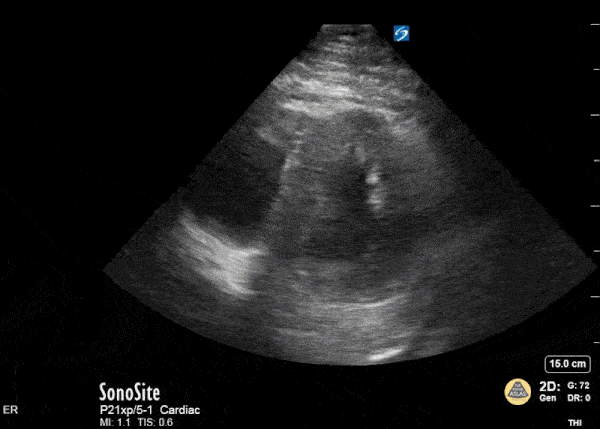

Right Ventricular Dysfunction - The D Sign

This is a parasternal short axis view in a patient with extensive pulmonary emboli on CT angiogram of the chest. The troponin was mildly elevated and patient hemodynamically stable. A bedside echo revealed evidence of RV strain (note the ā€œDā€ shaped left ventricle). Therese Mead, DO Emergency Physician